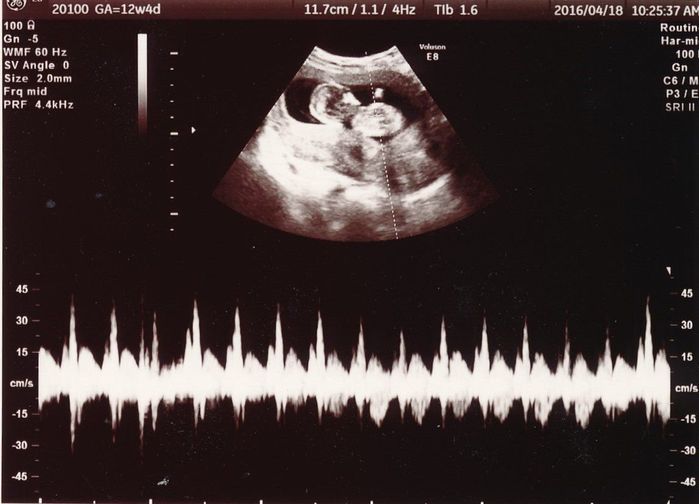

妊娠12週目のエコー写真

こちらの写真では、赤ちゃんの心拍が写っています。頭が左で体が右です。食事内容や生活習慣に加えて、仕事量が多くなりすぎないように気をつけていました。